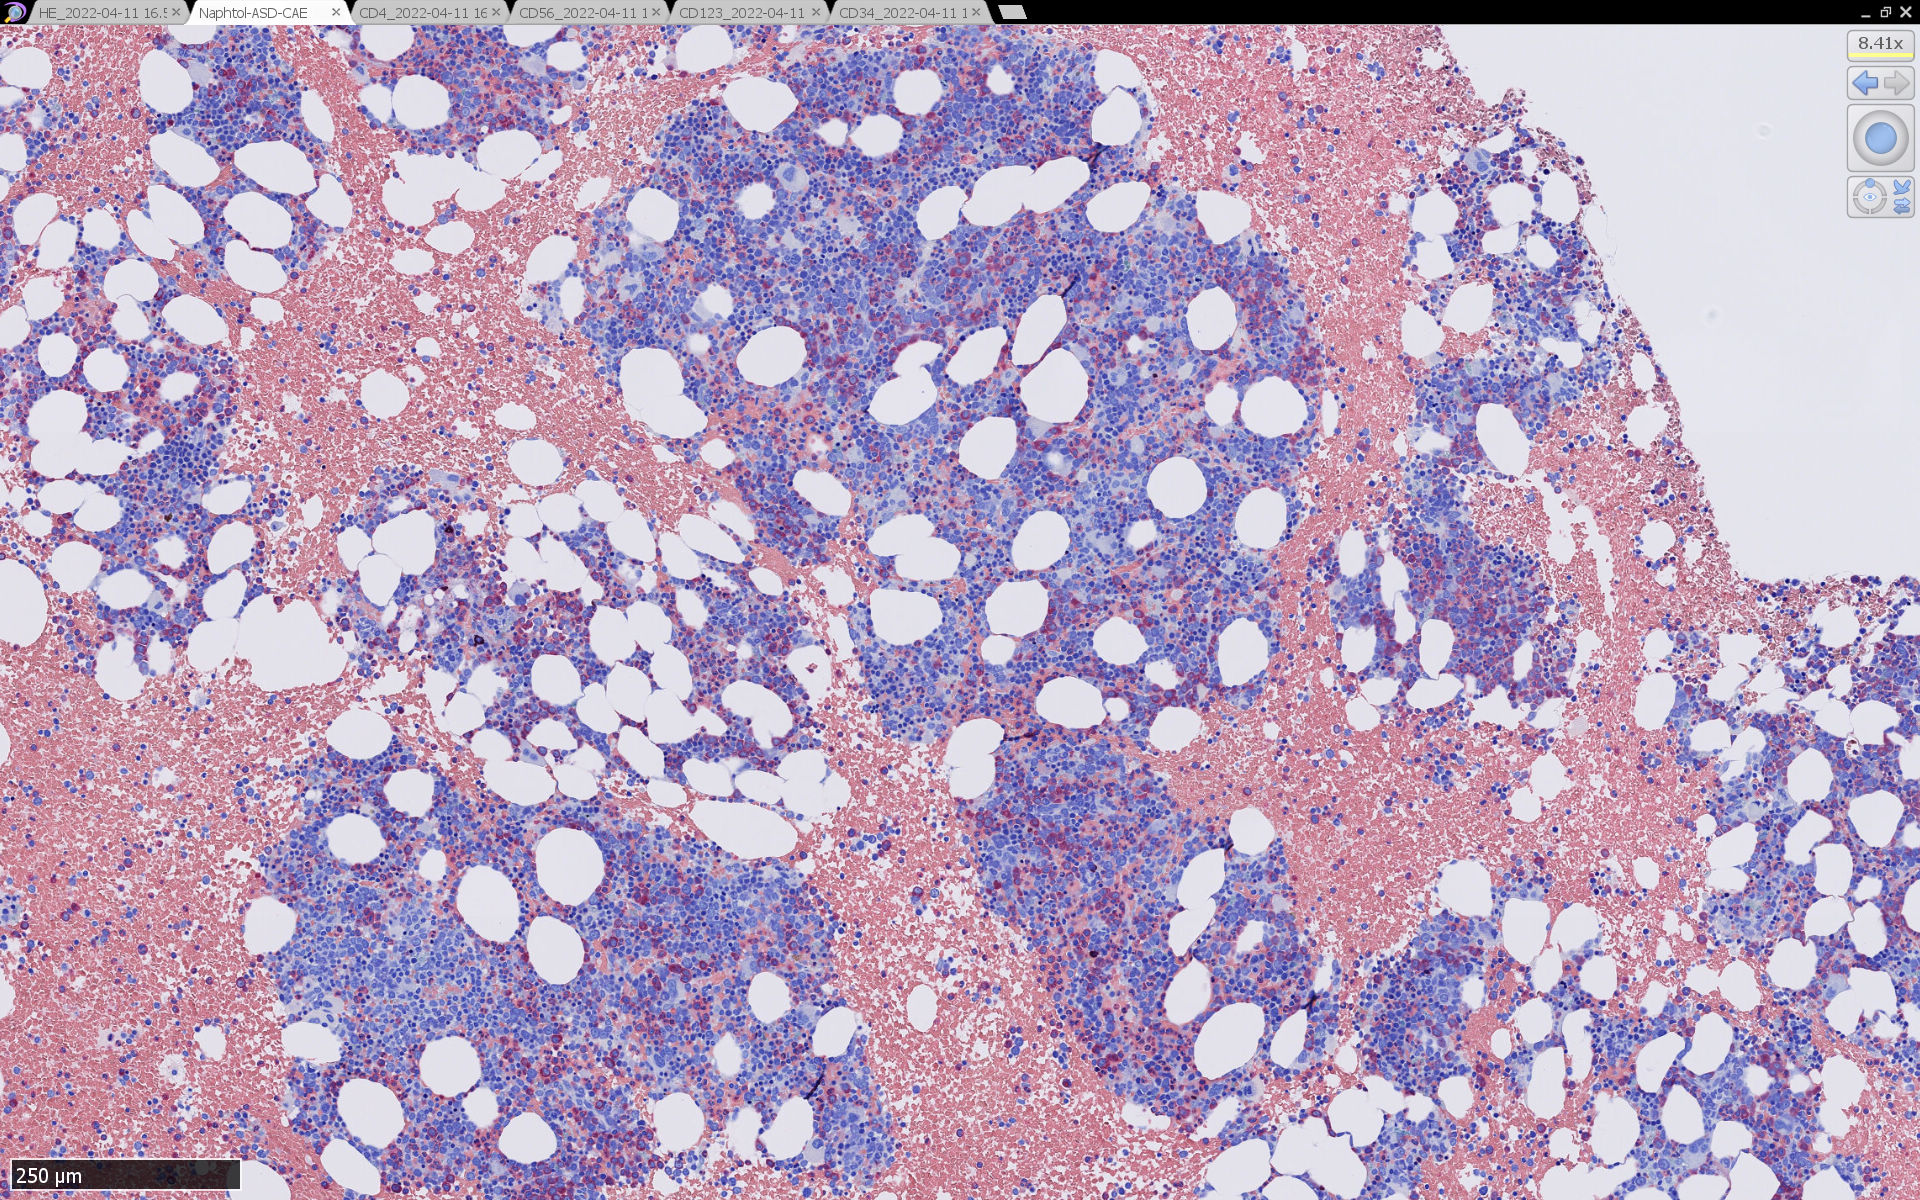

骨髄病理所見

HEでは腫瘍細胞の同定が難しい. 本症例は ASD-Giemsa染色を見ても, 腫瘍胞巣はよくわからなかった. 皮膚が先に診断がつき, 次いでBone marrowだったため, 免疫染色にすすめたが, Bone marrowが先だと診断に困ったかもしれない.

免疫染色

CD4は染まりすぎの感がある(濃く染まる細胞はCD4+ T-cellかもしれない). CD56, CD123が陽性で可能性が高くなり, BPDCNの診断にはCD34は陰性であることが必要

TCF4、CD123、TCL1をconsultationにより染色していただき, 陽性を確認した. CD34-, lysozyme-, CD123(おいてある病院は少ないかも)をしらべて, BPDCN研究会あてconsultationをする流れでしょうか.